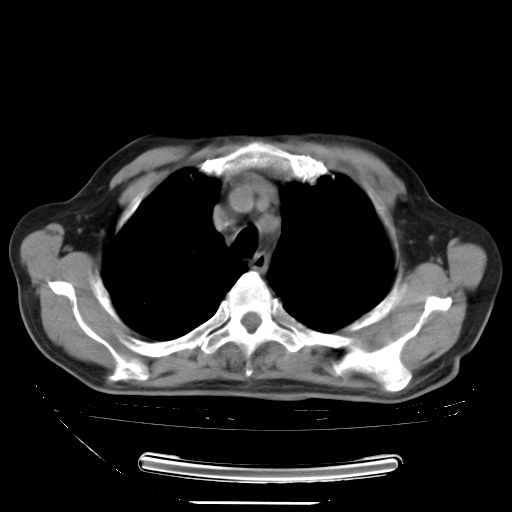

今天复查肺部CT,发现双肺广泛磨玻璃样改变。所以我把3月19日和5月9日相隔50天的肺部CT上传。请大家会诊。

5月9日肺部CT(在4月27日齐鲁医院肺部CT描述部分肺组织磨玻璃样改变,12天后肺组织广泛磨玻璃样改变)

2009年5月9日肺部CT

大致读了系列胸部CT:纵隔窗无明显异常,肺窗:从4、27至今:主要是双肺中下野外带可见毛玻璃样改变,目前处于急性肺泡炎阶段,至于原因考虑1、结替组织或胶原血管性疾病所致?2、恶性疾病如恶组在肺部所致的表现或细支气管肺泡癌?3、药物或其它原因如肺蛋白沉着症所致肺泡炎目前不太可能?总之,明天就去请我院的呼吸科、感染科、血液科和临免专家会诊哈。